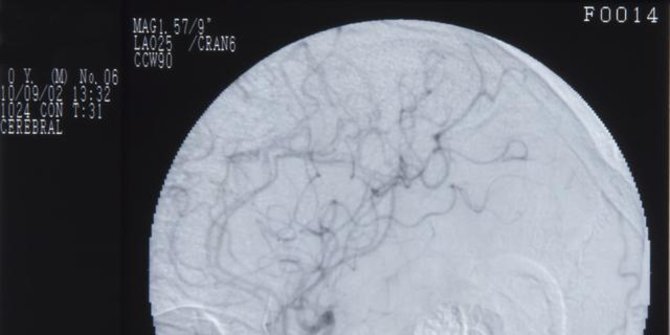

Terapi cuci otak ini pada dasarnya adalah metode diagnostik Digital Substraction Angiography (DSA), yg dalam bidang neurologi (ilmu saraf) dikenal dengan istilah cerebral angiography (CA).

Mengutip Healthline, cerebral angiography adalah tes diagnosis yg dikerjakan memakai X-ray. Metode ini mulai memproduksi gambar (cerebral angiogram) yg mulai menolong dokter menemukan penyumbatan atau ketidaknormalan yang lain pada pembuluh darah di kepala dan leher.

Penyumbatan dan ketidaknormalan di kepala dan leher dapat berujung jadi stroke atau pendarahan di otak.